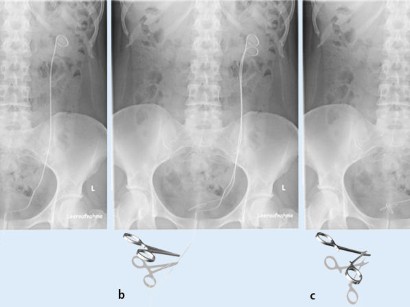

Doppel j schiene entfernen. Einführen des Doppel-J über den Arbeitsdraht in das Nierenbecken nochmalige Röntgenkontrolle bei richtiger Lage. Nach Abschluss der Behandlung zB. Es kommt auch immer darauf an ob der Arzt sein Handwerk beherrscht.

Nach einsetzen meiner Schiene konnte ich 3 Tage nicht arbeiten. Beim Vorschieben ist darauf zu achten dass der Arbeitsdraht stets gestreckt bleibt und keine Schleifen in der Harnblase bildet. Beim ersten mal war ein 3mm großes Stück vom Stein wohl doch übersehen worden und in die Harnröhre gerutscht wo es stecken geblieben ist.

Durchmessendes vorgeformtes Plastikröhrchen individueller Länge das zystoskopisch unter Sicht in einen Harnleiter eingebracht wird und sich am kranialen Ende im Nierenbecken am kaudalen Ende in der Harnblase für wenige Zentimeter aufrollt. Der DJ Stent sorgt für einen ungehinderten Urinabfluss und ist hierzu an den Enden mit kleinen Löchern versehen durch die die Nierensteine auch nach einer eventuellen Zertrümmerung nicht den harnabfluss behindern können.

Einführen des Doppel-J über den Arbeitsdraht in das Nierenbecken nochmalige Röntgenkontrolle bei richtiger Lage. Beim Vorschieben ist darauf zu achten dass der Arbeitsdraht stets gestreckt bleibt und keine Schleifen in der Harnblase bildet. Grundsätzlich sollten Sie mit Ihrem Urologen sprechen ob nicht die Zeit bis zur Doppel-J-Entfernung verkürzt werden kann. Sie sind in allen körperlichen Aktivitäten durch die Schiene nicht eingeschränkt. Dank der Doppel-J Schiene ist der Weg von der Blase zur Niere offen und damit der Urin nicht wieder zurück in die Niere fließt schlafe ich seit dem. In diesem Fall steigern Sie Ihre Trinkmenge und beobachten ob der Urin wieder heller wird. Der so gebildete doppelte Ringelschwanz pigtail. Die DJ-Harnleiterschiene ist ein dünnes meist 7 Charr. Es kommt auch immer darauf an ob der Arzt sein Handwerk beherrscht.

Durchmessendes vorgeformtes Plastikröhrchen individueller Länge das zystoskopisch unter Sicht in einen Harnleiter eingebracht wird und sich am kranialen Ende im Nierenbecken am kaudalen Ende in der Harnblase für wenige Zentimeter aufrollt. Der DJ Stent ist also in der Behandlung der Nierensteine eines der wichtigsten Hilfsmittel. Sie sind in allen körperlichen Aktivitäten durch die Schiene nicht eingeschränkt. Im Dämmerschlaf machen lassen. Die Entefernung der DJ Schiene ist nicht unbedingt sehr angenehm aber auch nicht unaushaltbar schmerzhaft. Am nächsten Tag bekam ich unter Narkose eine Doppel-J-Schiene von der Niere bis in die Harnblase gelegt. Der DJ Stent sorgt für einen ungehinderten Urinabfluss und ist hierzu an den Enden mit kleinen Löchern versehen durch die die Nierensteine auch nach einer eventuellen Zertrümmerung nicht den harnabfluss behindern können.